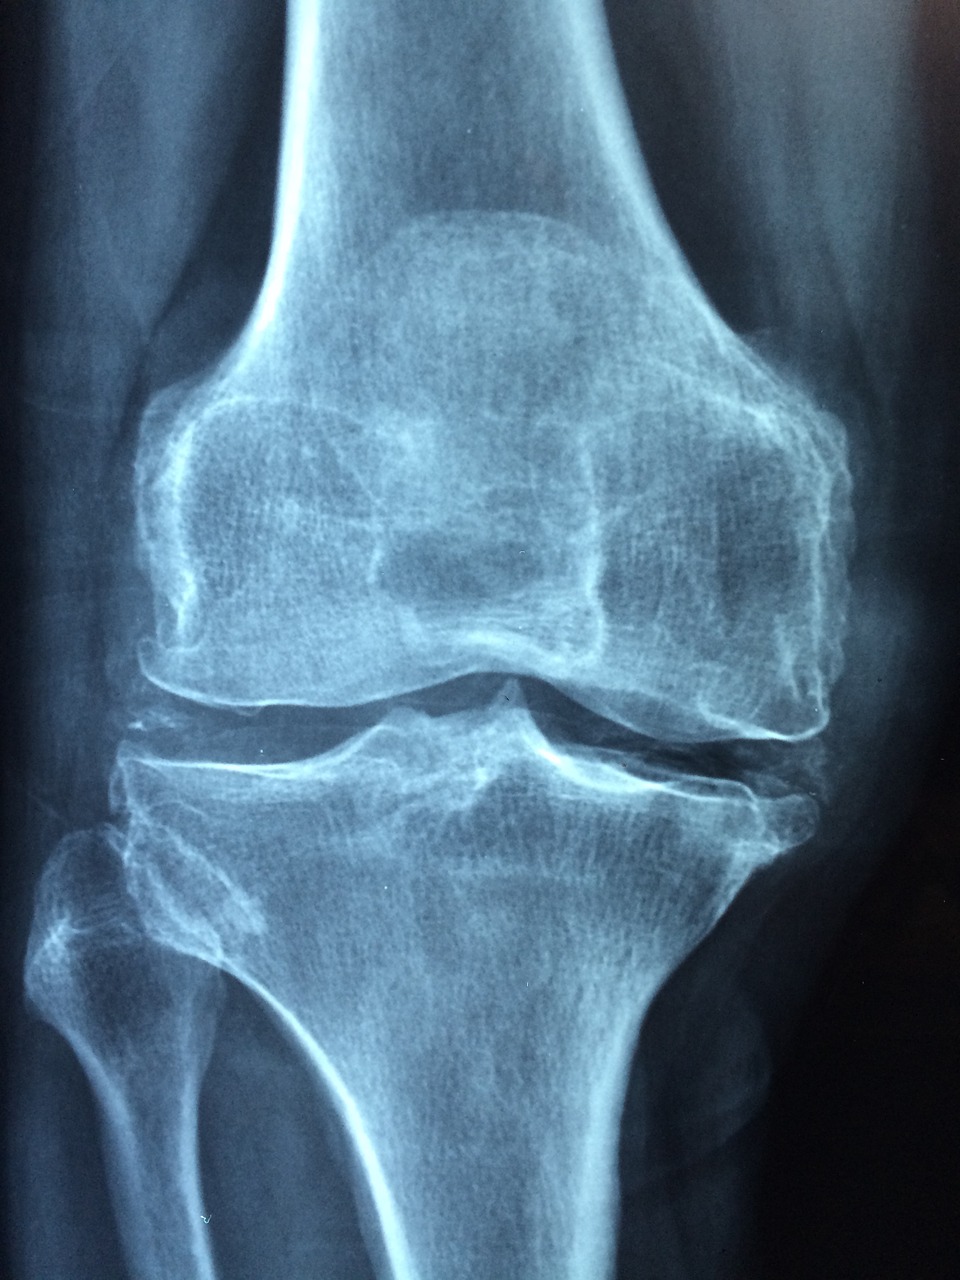

L’arthrose est une maladie que nous connaissons tous de nos jours, elle atteint les articulations du corps. Ce sont les cartilages au niveau des articulations qui sont victimes de dégénérescence, sans inflammation ou infection particulière visible cependant. C’est seulement au niveau des articulations que les douleurs se ressentent.

Bien des gens pensent que rester au repos va réduire les douleurs de l’arthrose, ce n’est cependant pas le cas. Au contraire, c’est une activité régulière qui pourra vous aider à lutter contre les effets de l’arthrose sur votre corps. Vous devez maintenir une activité physique douce pour rester en bonne forme, renforcer votre musculature, favoriser la réparation des cartilages et bien d’autres encore.

Le sport vous aidera aussi à préserver votre santé et votre corps de manière générale, notamment au niveau du système vasculaire. Ensuite, cela permet de préserver l’amplitude et la souplesse au niveau des articulations que la maladie attaque. Sachez cependant que seules les douleurs aigües provoquées par l’arthrose peuvent vous conduire à observer un repos strict, de quelques jours seulement.